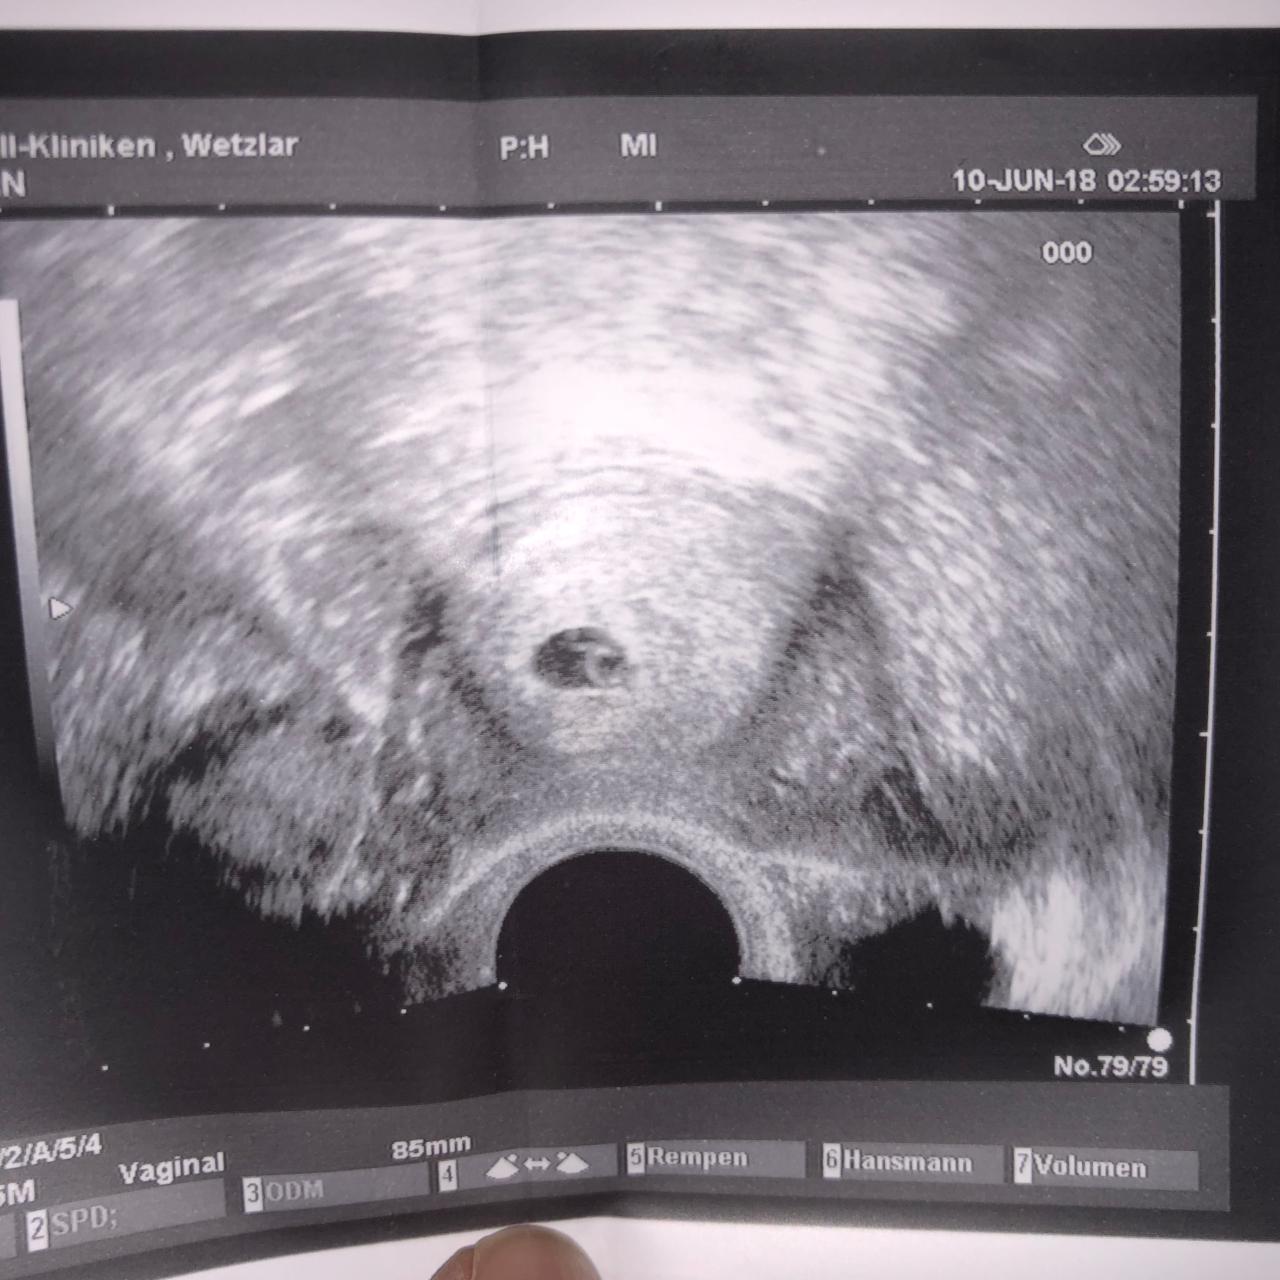

6 Ssw Nichts Auf Ultraschall Zu Sehen. Außerdem kann durch die zusätzliche dopplersonographie. Zwischen der 11+0 und 13+6 ssw wird ein früher fehlbildungsultraschall durchgeführt.

Zwischen Der 11+0 Und 13+6 Ssw Wird Ein Früher Fehlbildungsultraschall Durchgeführt.

Das liegt nicht daran, dass die schwangere jetzt “für zwei essen” muss, sondern am hormonhaushalt, der kräftig durcheinandergewürfelt wird, um dem neuen bauchbewohner ein sicheres und gutes umfeld. Bestimmte messwerte des ultraschalls werden in kombination mit der bestimmung der blutwerte papp a und hcg und anderen faktoren zu einer risikoberechnung für das vorliegen einer trisomie 13, 18 und 21 kombiniert. Bonifatius hospitalgesellschaft lingen, der als freigemeinnütziger kirchlicher träger vier allgemeinkrankenhäuser sowie verschiedene ambulante und stationäre einrichtungen der altenpflege und altenhilfe betreibt.

Außerdem Kann Durch Die Zusätzliche Dopplersonographie.